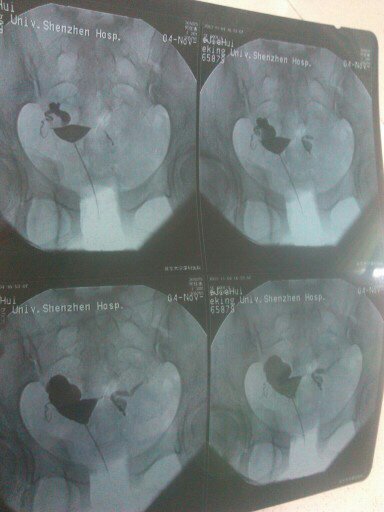

两年不孕,去年做了两次通水医生说通了,检查很多还是一直怀不上。这星期做了造影,结果两边都阻塞了。医生要我做腹腔镜手术治疗,我觉得手术对身体有影响,想问下我这样子的做通水吃中药能不能治好?感谢!